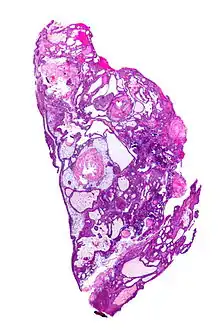

| Very low magnification micrograph of an adamantinomatous craniopharyngioma. HPS stain. | |

Micrograph showing the characteristic features of an adamantinomatous craniopharyngioma - cystic spaces, calcifications, and "wet" keratin, HPS stain